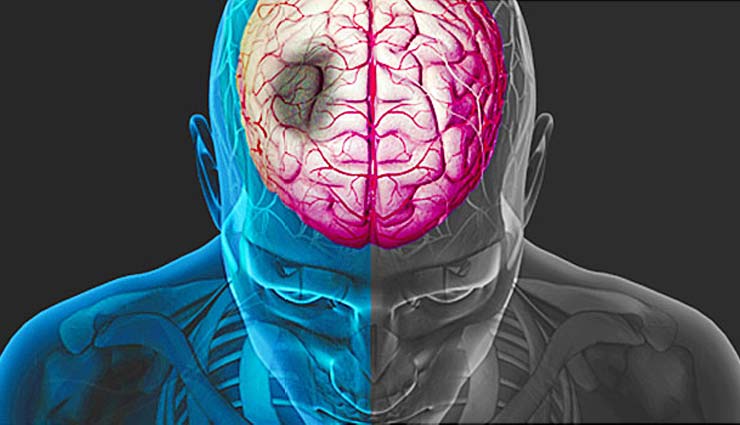

स्ट्रोक

स्ट्रोक या मस्तिष्काघात एक चिकित्सीय स्थिति है जिसमे मस्तिष्क मे खराब रत्क प्रवाह कोशिका मृत्यु मे परिणाम देता है । इसे मस्तिष्क का दौरा भी कहा जाता है।स्ट्रोक के दो मुख्य प्रकार है :रक्त प्रवाह की कमी के कारण इस्किमिक और राक्त्स्त्राव के कारण हीमोराजिक। स्ट्रोक के लक्षणो मे शरीर के एक तरफ स्थानांतरित करने या महसूस करने मे असमर्थता ,समझने या बोलने मे समस्या ,चक्कर आना या दृष्टि के नुकसान शामिल होते है । स्ट्रोक होने के तुरंत बाद उसके लक्षण अक्सर प्रकट होते है।यदि लक्षण एक या दो घंटे से भी कम समय तक चलते है तो इसे मिनी स्ट्रोक भी कहते है। यह बीमारी भी सबसे ज्यादा बुजुर्गों को प्रभावित करती है।